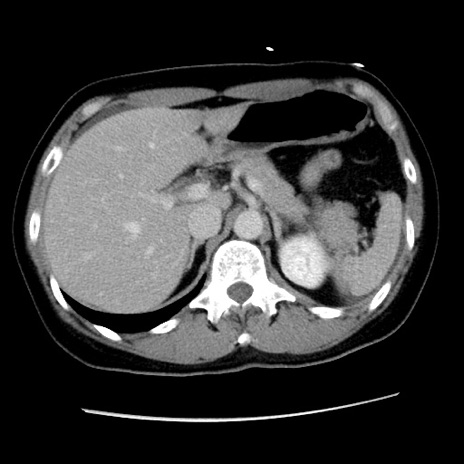

症例10(横断像)

【症例】 50歳代女性

【主訴】 腹痛

【現病歴】前日生レバーを食べた。今朝に排便あり。 昼前に突然発症の腹痛を生じ、当院救急外来を受診した。

【既往歴】 子宮筋腫にてで子宮全摘後

【身体所見】 意識清明、腹部:平坦、軟、下腹部やや左を中心に圧痛・反跳痛あり、筋性防御あり

【データ】WBC 7800、CRP 0.07